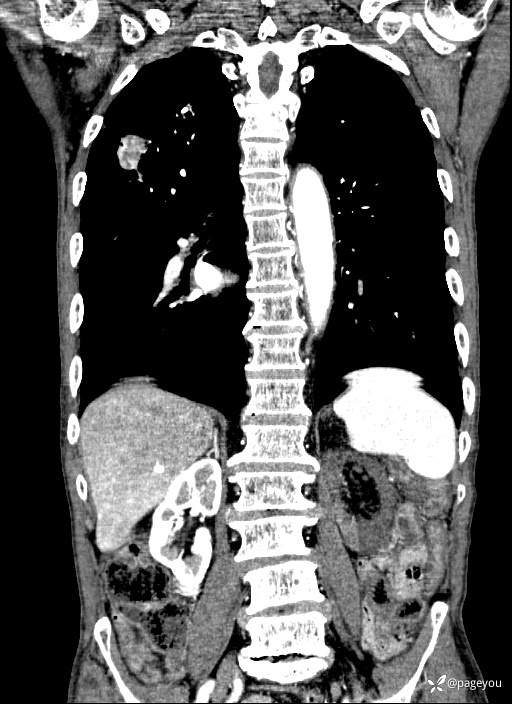

主动脉CTA: